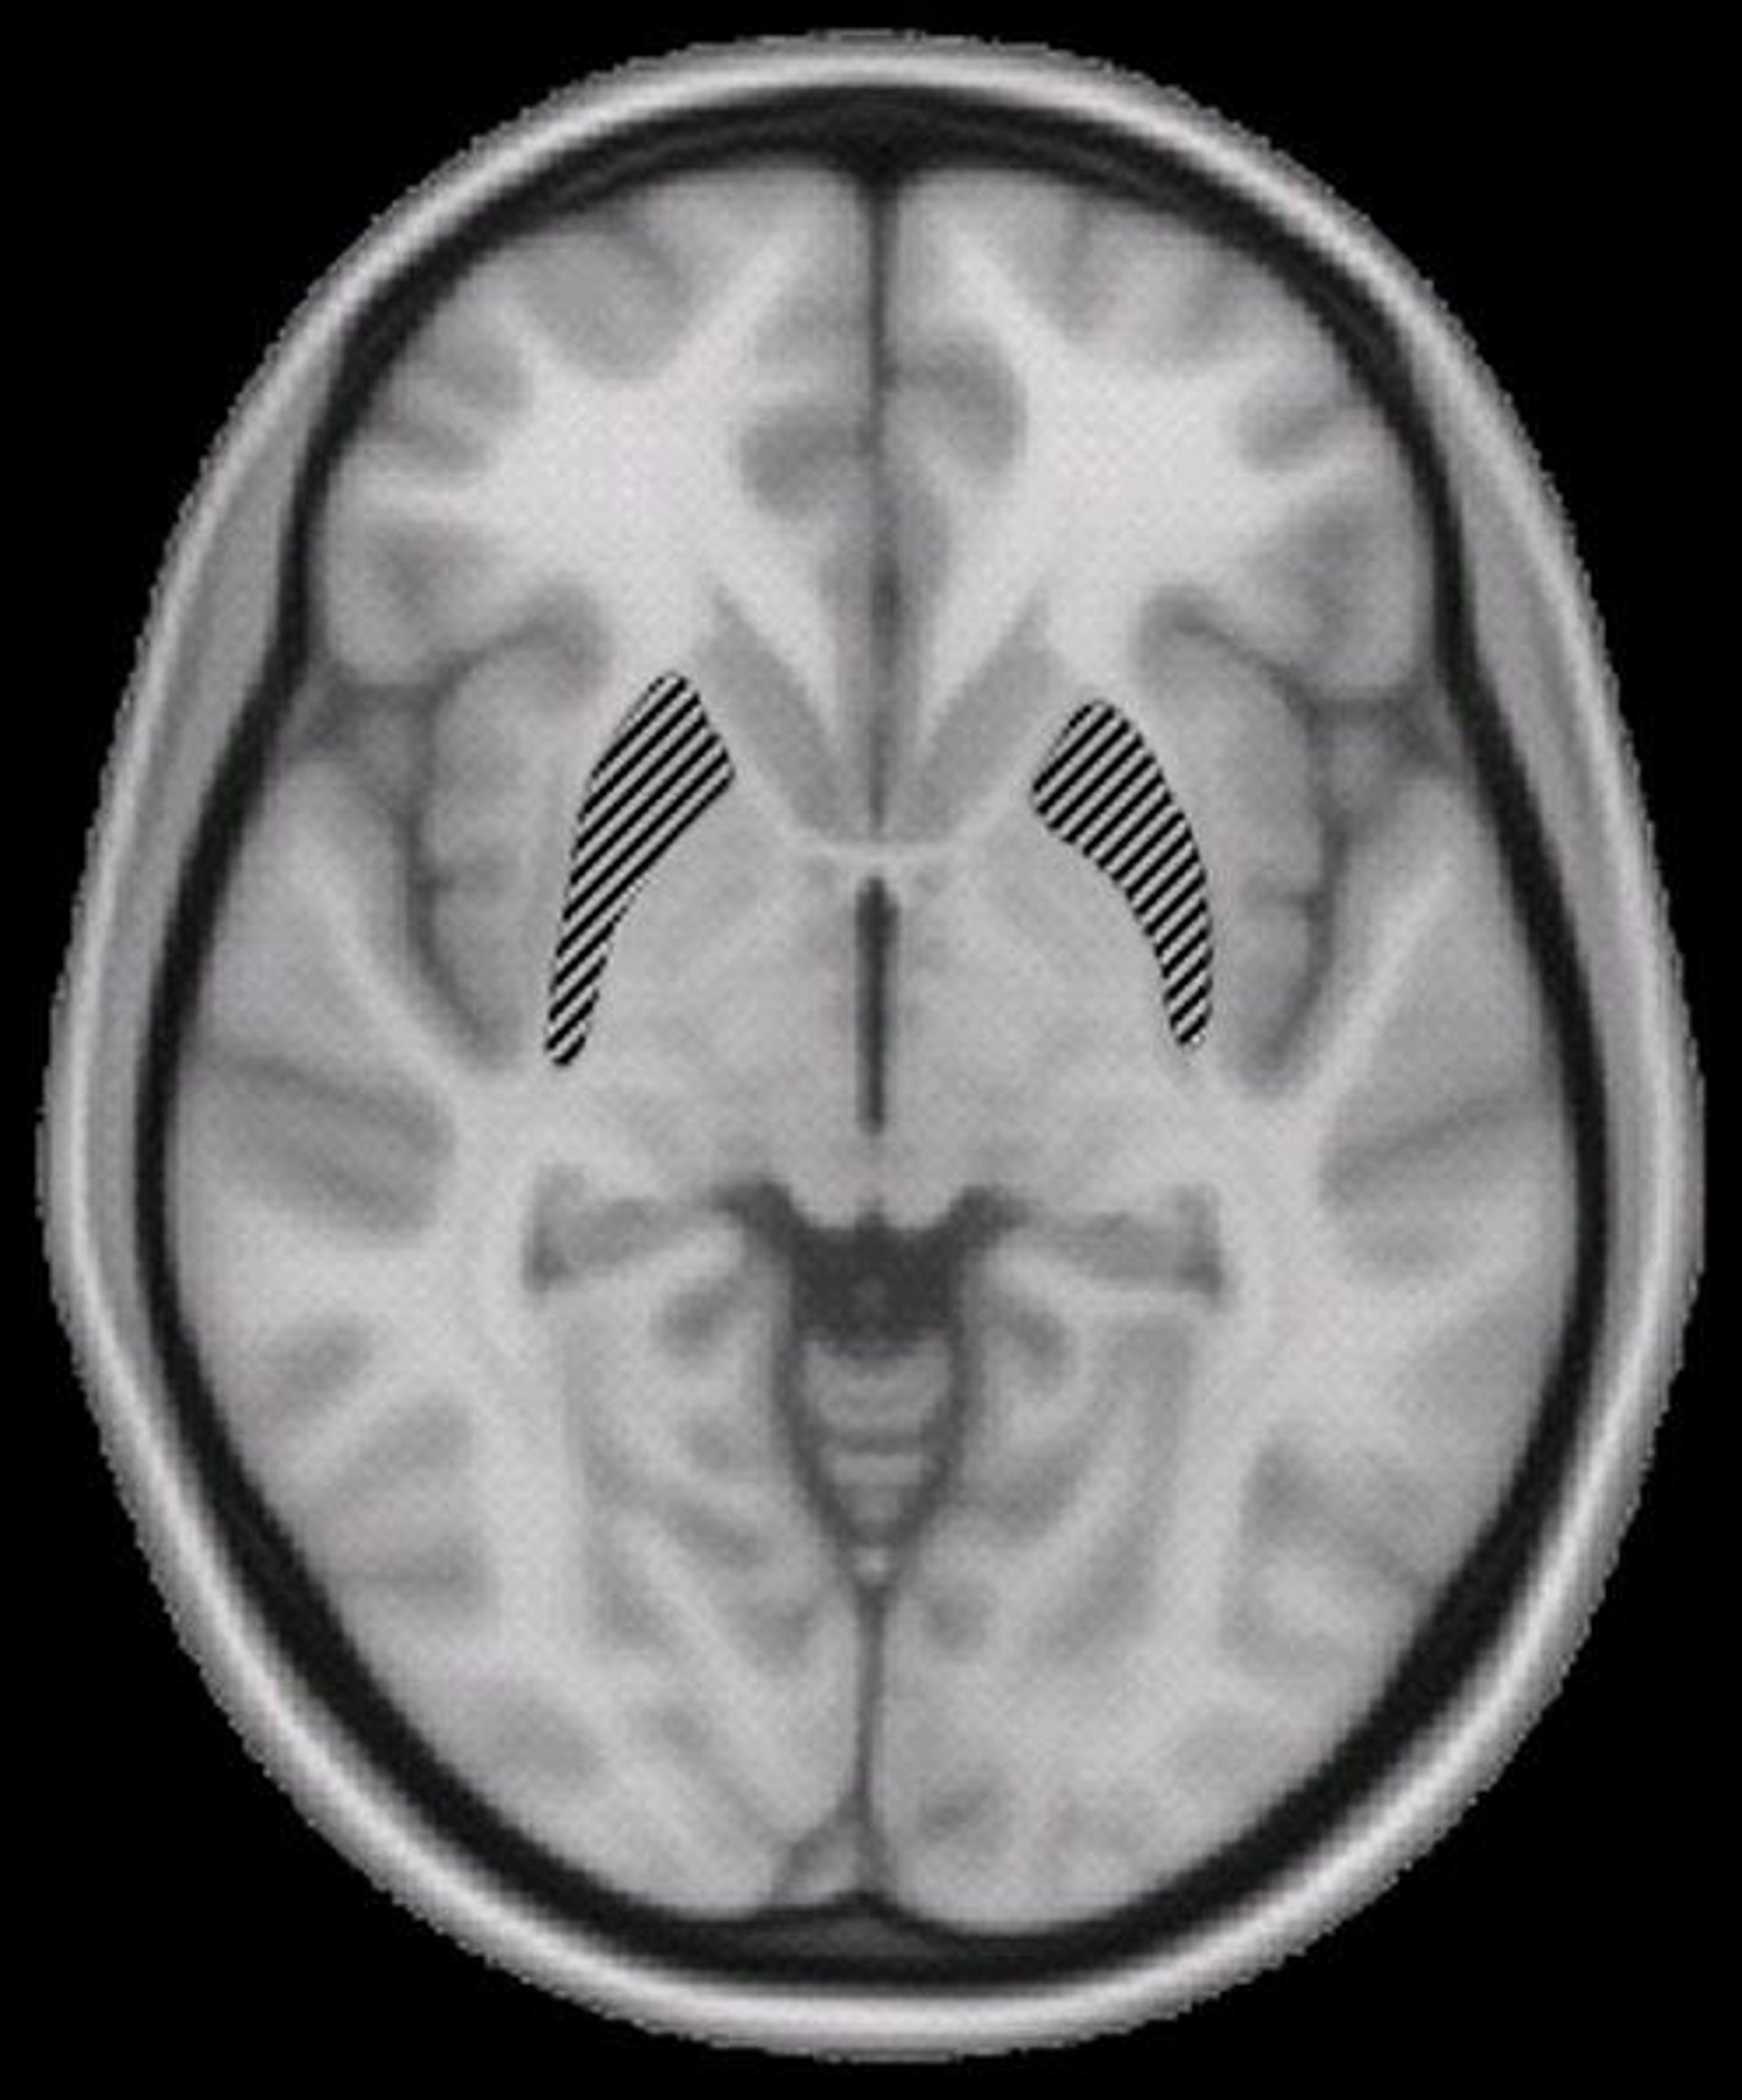

Los científicos, dirigidos por Sylvain Charron y Etienne Koechlin, utilizaron imágenes de resonancia magnética funcional o IRMf para controlar la actividad en el cerebro de voluntarios que realizaban tareas de emparejamiento de letras.

Cuando los voluntarios completaban una tarea a la vez, ambos lados del cingulado anterior dorsal y la corteza promotora estaban activos. Sin embargo, cuando completaban dos tareas de forma simultánea, la actividad en estas regiones de la izquierda correspondían con la tarea primaria y la actividad en la derecha correspondía con la tarea secundaria.

Según los autores, esta división del trabajo entre los dos lados podría clarificar varias limitaciones en la toma de decisiones y las capacidades de razonamiento en humanos.